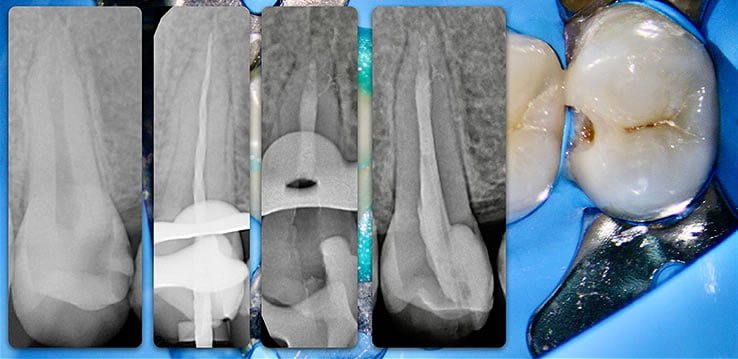

Template for x-rays

Biolight® DRILL-FREE posts are available in bundles of 4, 6, 9 and 12 strands. The post size is selected based on the width of the canal at the coronal area. Depending upon the canal width at the apical stop, a certain number of strands must be pushed to the stop. Both of the measurements are made with the assistance of a radiograph and the template that is included in the TRAINING KIT.